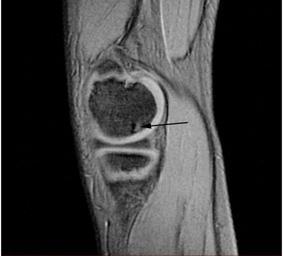

MAKE A MEME View Large Image OCD WalterReed MRI-Sagital-T2.jpeg en Sagittal and coronal T1 and T2 images demonstrate linear low T1 high T2 signal at the articular surfaces of the lateral aspects of the medial femoral condyles bilaterally corresponding to the ...

Keywords: OCD WalterReed MRI-Sagital-T2.jpeg en Sagittal and coronal T1 and T2 images demonstrate linear low T1 high T2 signal at the articular surfaces of the lateral aspects of the medial femoral condyles bilaterally corresponding to the radiographs confirming the presence of bilateral osteochondritis dissecans with diffuse increase in T2 signal at the medial femoral condyles indicating marrow edema From the case of a 9-year-old boy with bilateral knee pain Uniformed Services University Obtained from MedPix Database http //rad usuhs mil/medpix/medpix_image html imageid 14470 Pil Kang 2003-02-04 PD-USGov Magnetic resonance imaging of the knee MRI of osteochondritis dissecans